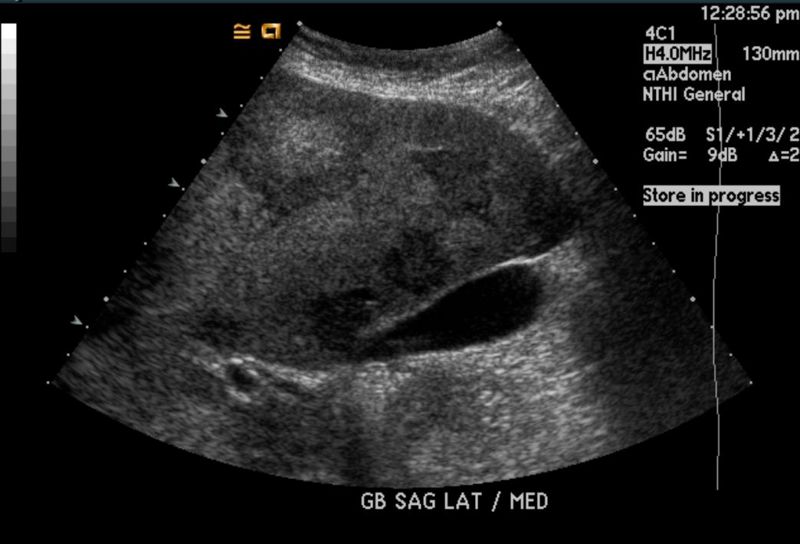

El ultrasonido hepatobiliar es un estudio de imagen que utiliza ondas sonoras de alta frecuencia para generar imágenes en tiempo real de los órganos del sistema hepatobiliar. Esta técnica es completamente no invasiva y no utiliza radiación, lo que la hace especialmente adecuada para pacientes pediátricos, mujeres embarazadas y aquellos que requieren estudios de monitoreo frecuentes.

Este examen permite evaluar el tamaño, la forma y la textura del hígado, así como la presencia de cálculos en la vesícula biliar, obstrucciones en los conductos biliares y otras anomalías estructurales. El procedimiento es sencillo, rápido y generalmente indoloro, con una duración promedio de 15 a 30 minutos.

El ultrasonido hepatobiliar se recomienda como primera línea de estudio en diversas condiciones debido a su accesibilidad, rapidez y seguridad. Entre las principales indicaciones se encuentran:

- Evaluación inicial de dolor abdominal en el cuadrante superior derecho.

- Diagnóstico de colelitiasis, colecistitis y obstrucciones biliares.

Además, su capacidad para realizarse en tiempo real permite observar procesos dinámicos, como el flujo sanguíneo en el hígado mediante la técnica Doppler.

- Beneficios: Es seguro, económico, no invasivo y accesible en la mayoría de las clínicas y hospitales. No expone al paciente a radiación y es ideal para evaluaciones iniciales.

- Limitaciones: Su resolución es menor en comparación con la tomografía. Además, su eficacia puede disminuir en pacientes con obesidad o con acumulación de gas intestinal.